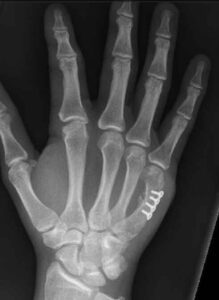

- XRAY – gold standard metacarpal fracture diagnosis

Open reduction or internal fixation (surgery) by an orthopaedic surgeon. Following surgery, you will be placed into a custom Thermoplastic splint fabricated by the hand therapist at Action Rehab Hand Therapy Clinic and an exercise program will begin.

See below the two treatment approaches for a patient who has metacarpal fracture.

Fig 1: Basic Treatment

An off-the-shelf splint is being used to treat a metacarpal fracture. It does not hold the metacarpal in a stable position leading to possible complications.

Fig 2: Action Rehab Hand Therapy Clinic Treatment

Your Action Rehab Hand Therapy Clinic hand therapist will fabricate a custom thermoplastic splint which will allow for healing and union of the fracture, followed by an array of ranging and stability exercises. The primary goals of treatment are to achieve acceptable alignment, stable reduction, strong bony union, and unrestricted motion.